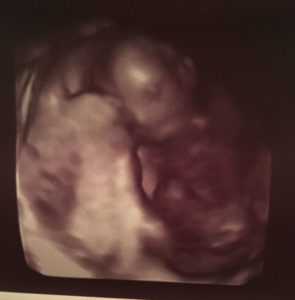

We’re now 18 weeks pregnant with a baby girl!